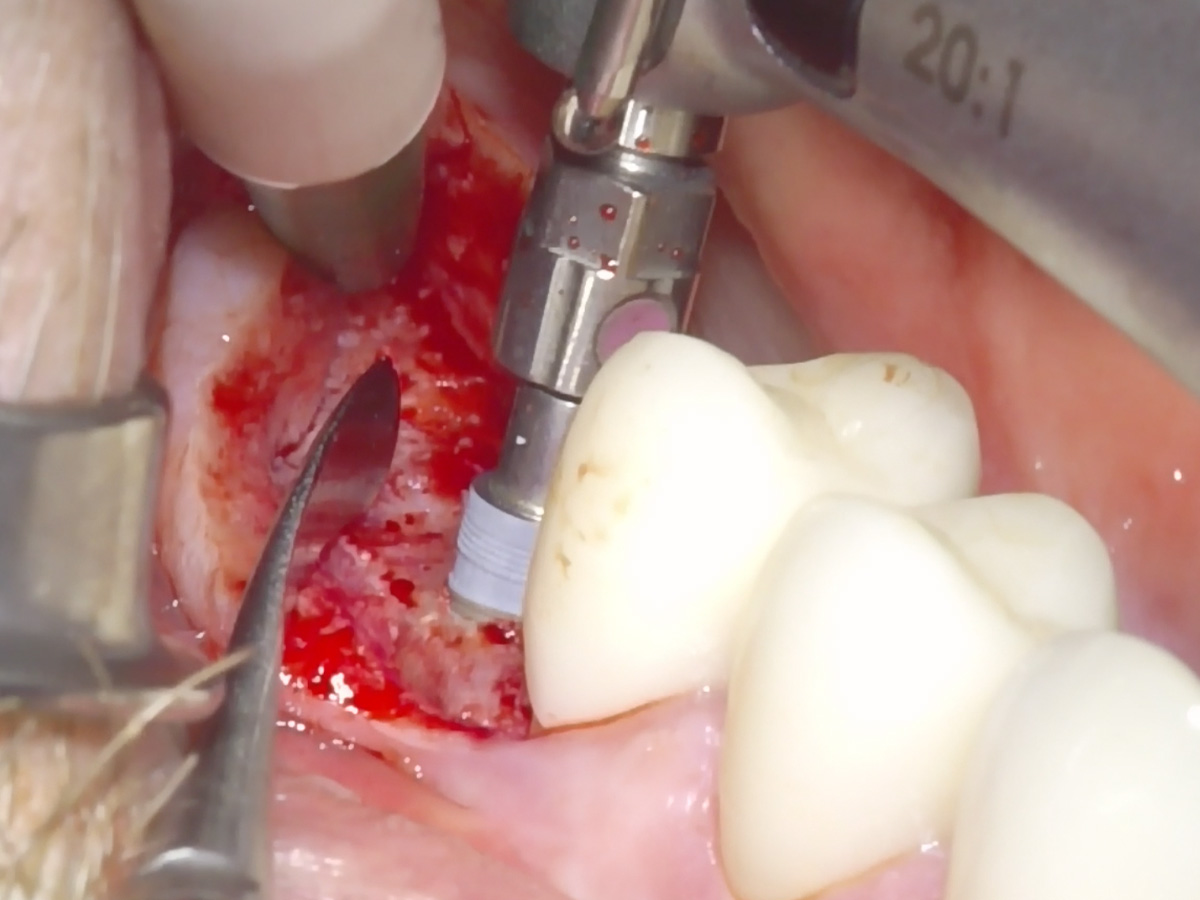

Abbildung 3

Sinusbodenaugementation mit xenogenem Material (Apatos Mix; 10 % Eigenknochen aus Zugangspräparation beigemischt).